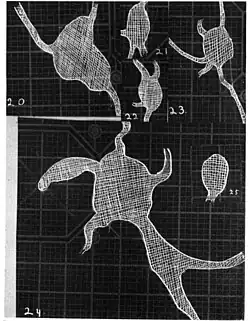

20. Venous engorgement. 21. After pressure over internal 22. Same case, normal. 23. Scotoma after ligation of common carotid. 24. Edematous swelling of nerve and retina. 25, Normal blind spot of other eye.

20. Venous engorgement. 21. After pressure over internal 22. Same case, normal. 23. Scotoma after ligation of common carotid. 24. Edematous swelling of nerve and retina. 25, Normal blind spot of other eye. -